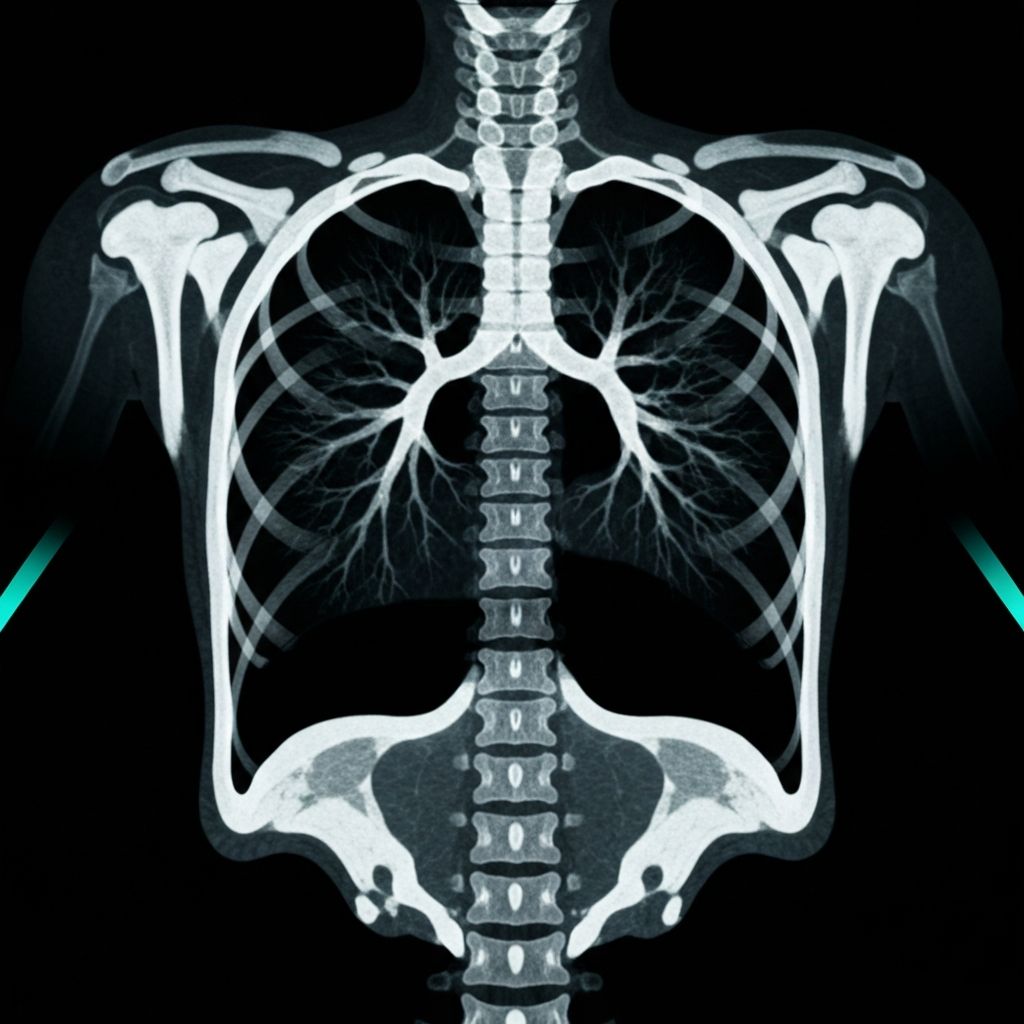

CT CHEST 2024

COMPARISON VIEW